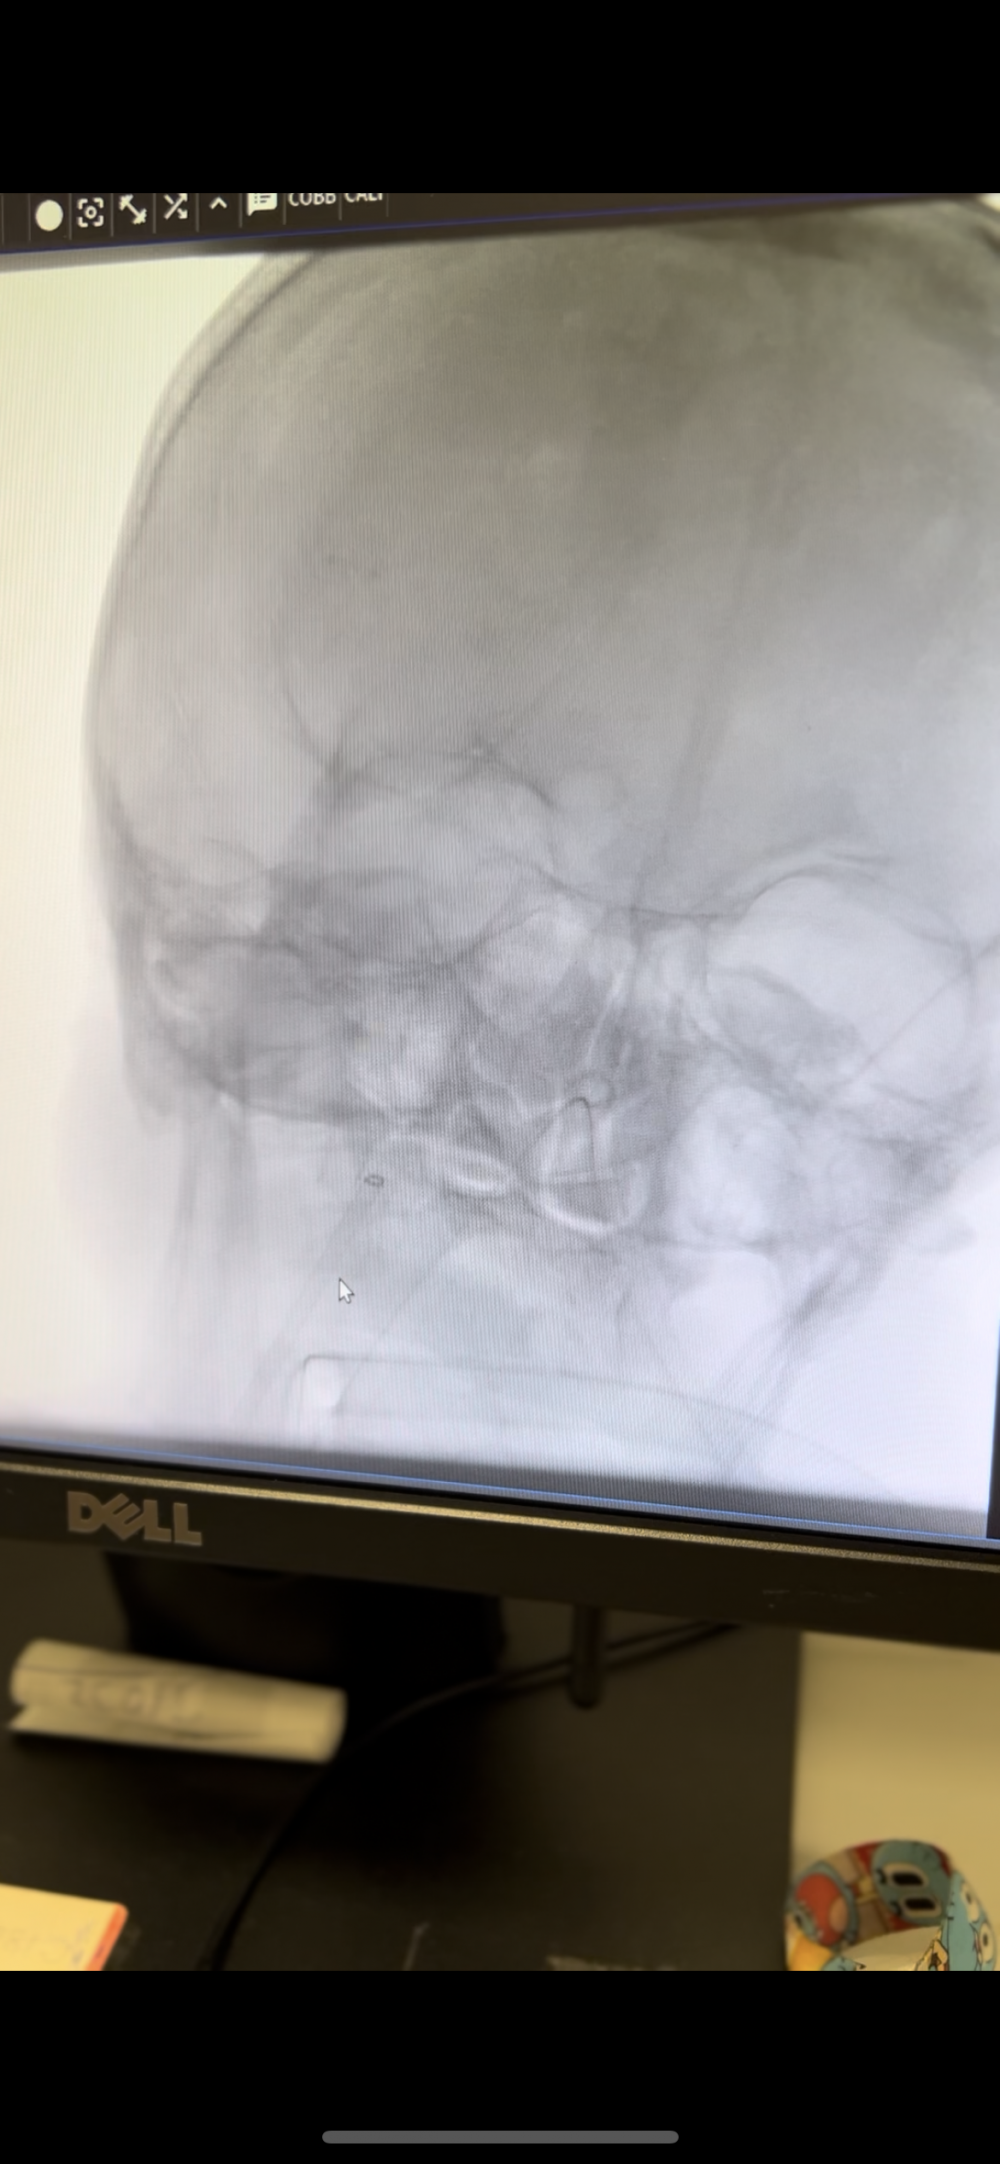

İnme semptomlarıyla hastaneye başvuran Sezer’in sağ kol ve bacağında güçsüzlük, konuşma bozukluğu ve bilinç bulanıklığı şikâyetleri bulunuyordu. Yapılan görüntülemeler sonucunda hastanın şah damarında tıkanıklık tespit edildi. Girişimsel Nöroloji Uzmanı Doç. Dr. Ezgi Sezer Eryıldız tarafından anjiyo ünitesinde acil olarak uygulanan trombektomi (damar tıkanıklığına yol açan pıhtının cerrahi olarak çıkarılması) işlemiyle hastaya müdahale edildi.

“Hastamız bize erken saatlerde ulaştı. Bilinç bozukluğu, konuşma sorunu ve bir tarafında güç kaybı vardı. Görüntüleme sonucunda şah damarında tıkanıklık olduğunu gördük ve hemen müdahale ettik. Trombektomi işleminin ardından dakikalar içinde felç belirtilerinin gerilediğini gözlemledik. Ardından inmenin nedenine yönelik tetkiklerimizi yaptık ve hastamızın tedavisini düzenledik. Şu anda günlük yaşamına bağımsız bir şekilde devam ediyor.”